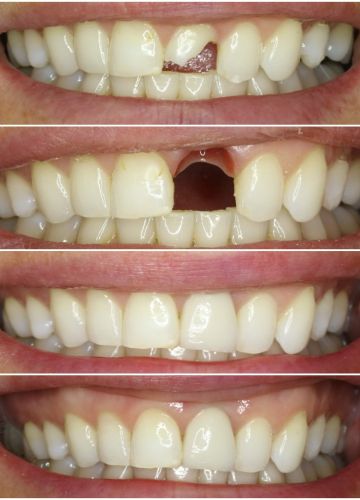

• Neatjaunojama zoba atraumatiska ekstrakcija (izraušana)

• Tūlītēja zoba implanta ievietošana un pagaidu kronīša (plastmasa) izgatavošana.

• Pēc 5 mēnešiem tika izgatavots slāņots cirkonijkeramikas kronis

• Tika  nomainītas vecās plombas priekšzobu rajonā